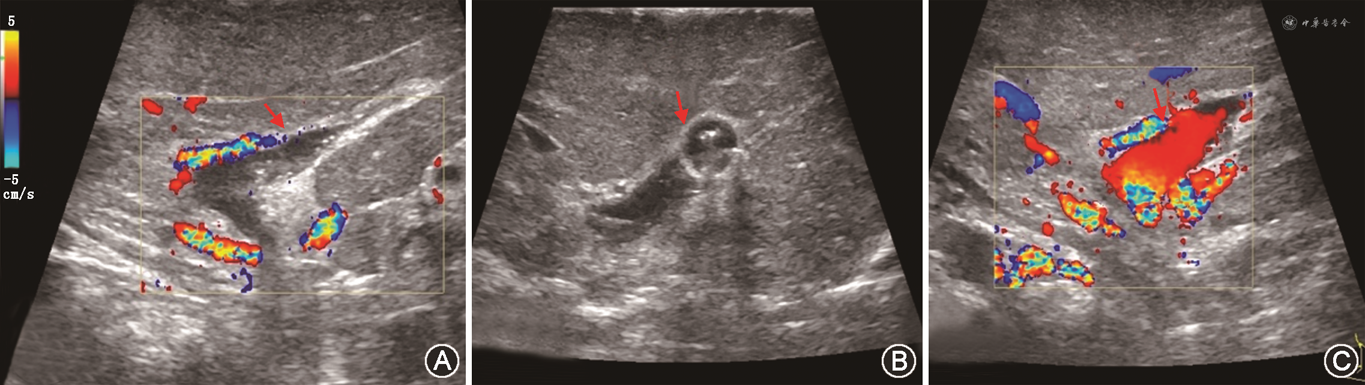

3. 门静脉评估:门静脉海绵样变为肝移植相对禁忌证,超声可明确显示,表现为第一肝门部门静脉主干及肝内门静脉分支周围出现广泛或局部蜂窝状血管结构。CDFI可见蜂窝状结构内充满红蓝相间血流,脉冲波多普勒成像可检测出静脉样血流信号。肝移植术前必须要了解肝硬化HCC患者是否存在门静脉栓子(portal vein thrombosis,PVT),并确定其是否源于肿瘤,以排除移植禁忌证[32]。肿瘤性PVT在灰阶超声表现为门静脉主干或肝内分支扩张伴有腔内实性回声,CDFI可在肿瘤性PVT内测及动脉频谱(灵敏度24.0%,特异度100%)[33, 34],超声造影表现为动脉期肿瘤性栓子与肝动脉同时快速强化,门静脉期及延迟期出现造影剂廓清。移植肝供、受体术前超声评估主要内容如图4所示。

1. 评估内容:主要评估移植肝肝动脉、门静脉、肝静脉、下腔静脉吻合口及其近、远端血流情况,判断是否存在血管痉挛、扭曲、狭窄、血栓等异常情况(图5)。

(1)肝动脉:通常在移植肝第一肝门区检测肝动脉血流,肝右动脉可于肝内门静脉右支前方测量;肝左动脉可于门静脉左支矢状部旁测量(图8A)。移植术后肝动脉收缩期峰值流速(peak systolic velocity,PSV)变动范围较大,术后第一天PSV值可为19~133 cm/s[39, 40]。肝动脉RI正常范围为0.55~0.80,收缩期加速时间(systolic acceleration time,SAT)<0.08 s[41]。需注意的是,肝移植术后早期,肝动脉RI可较高,甚至可达到1.0,可能与术后血管痉挛、受体年龄偏高及供肝冷缺血时间过长等因素有关。对移植肝动脉RI异常患者应严密动态观察,结合患者病史、临床表现及其他影像学检查结果诊断及鉴别移植肝并发症[42]。评估流程如图7所示。

(2)门静脉:移植肝门静脉血流频谱呈向肝持续性单相波,血流流速可随呼吸轻微波动(图8B)。肝移植术后早期,门静脉流速有明显增高现象(PSV最高可达100 cm/s),甚至可以出现湍流,多数情况下会于3个月左右逐渐下降。这种移植术后早期门静脉流速增高的表现属正常现象,应注意与吻合口狭窄造成的流速增高相鉴别[43]。

(3)肝静脉及下腔静脉:正常肝静脉频谱具有期相性,反映血流随心动周期不同的生理变化(图8C)。可在距第二肝门2 cm内测量各支肝静脉流速及观察频谱形态,肝静脉流速变化范围较大(20~100 cm/s),多为三相波频谱。下腔静脉近心端流速曲线多为三相或双相波,少数呈单相波,流速变化范围大(30~100 cm/s)。